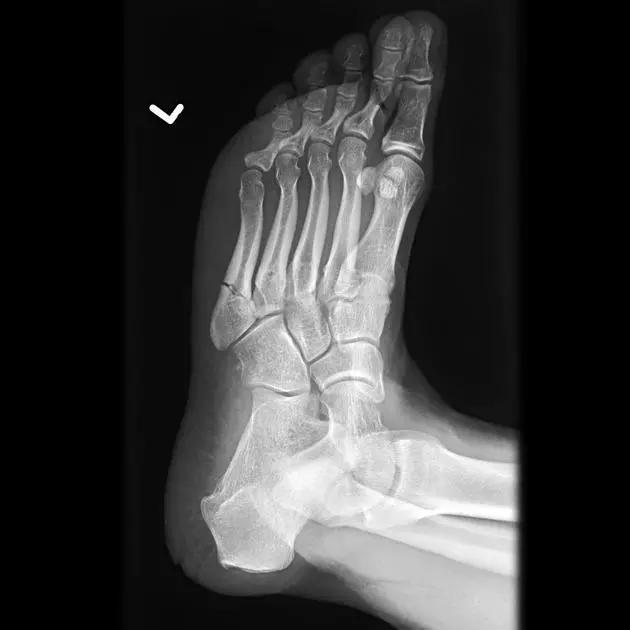

13. Lisfranc 骨折

骨折累及到足的跗骨关节。跖跗关节位于足的前部,是构成足纵弓及横弓的重要结构。

第一跖骨与第一楔骨组成鞍状关节,整个跖跗关节的稳定性,有赖于第一跖跗关节的稳定性,一旦第一跖跗关节发生脱位,其他 4 个跖跗关节容易发生脱位。第一跖跗关节的关节囊有背侧和跖侧副韧带增强,其内缘尚有胫前肌腱附着。第一、二跖骨基部无韧带相连,第一楔骨与第二跖骨基部间有坚韧的 Lisfranc 韧带相连,有助于第一跖跗关节的稳定性。第二楔骨较短,第二跖骨位于第一、二楔骨之间成为外力作用的支点。因此第二跖骨基底易发生骨折。

Lisfranc 关节复合体(Lisfranc joint complex)示意图:first metatarsal 第一跖骨;second metatarsal 第二跖骨;Lisfranc joint 利斯弗朗关节;first,second and third cuneiforms 第一,二,三楔骨;cuboid 骰骨